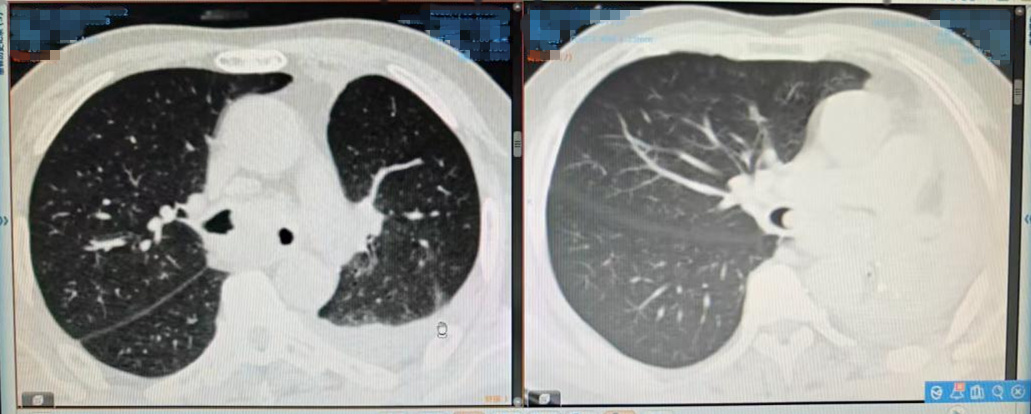

治疗前后影像结果对比。右图为治疗后,显示左肺完全复张,恢复功能。